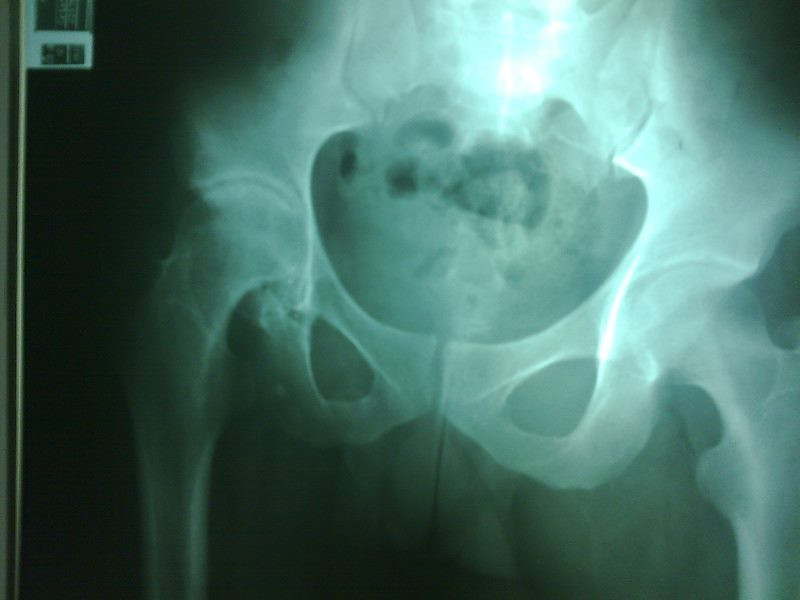

Radiografías con enfoque en fisiatría

Envíado por Dr. Hernán Darío Sánchez Ramos